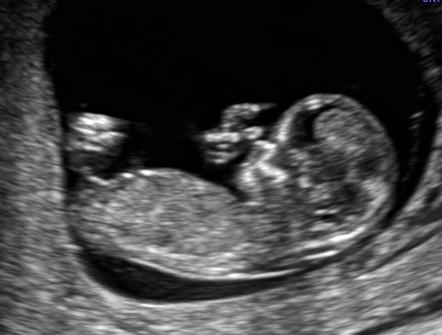

Slight boy lean x

Thank you for responding. I think top looks boy but the second pick has 3 lines which makes me think girl. Confusing. Again, thank you for your guess.

3 lines doesn't say anything on a side shot at 12 weeks. You need a potty shot at 15/16 weeks. Top one got me leaning boy but absolutely not sure!!

i think its probably a boy especially at 12 weeks gestation BUT nubs are never 100%, i hope you get what you want

I would lean boy. But it's hard to say for sure.